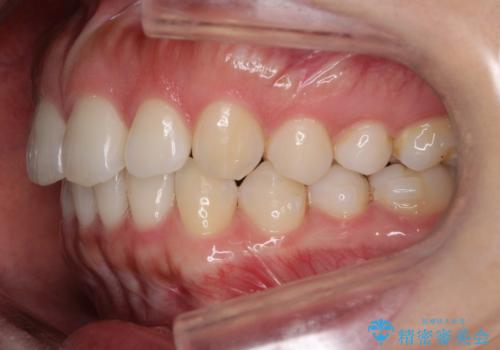

【前歯のガタガタが気になる】インビザライン症例

- 前歯の歯並びの改善を希望され来院された患者様です。

初診時の歯並びの状態としては、下顎前歯に及ぶの中等度のがたつき(叢生)があり、前歯が深く噛みこんでいる状態でした。

抜歯は行わず歯列弓の拡大やディスキング(歯と歯の間の隙間を作る処置)を行い叢生を改善しました。

矯正装置としてはマウスピースを使用しています。